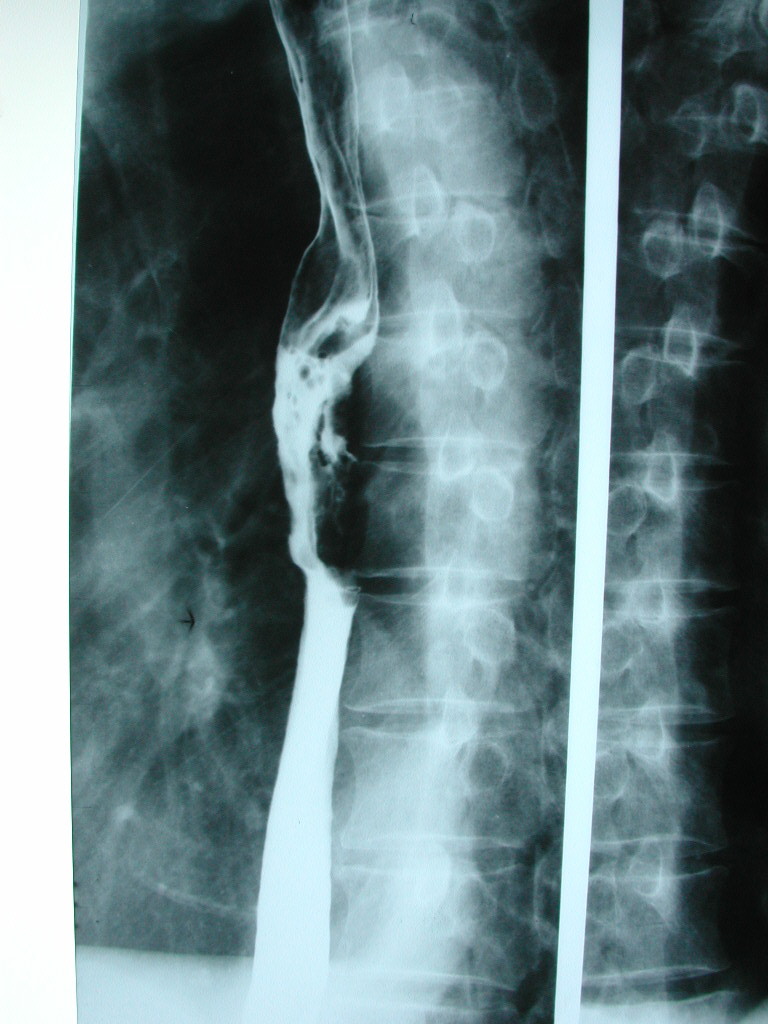

食管长度与身高有关,一般认为成人食管长度约为25cm,门齿距贲门约为40cm。

颈段食管:食管入口至胸廓上口,长约3cm,距门齿15-18cm

胸上段:胸廓上口至气管分叉水平,长约6cm,距门齿18-24cm

胸中段:气管分叉至贲门部中点的口侧段,长约8cm,距门齿24-32cm

胸下段:气管分叉至贲门部中点的肛侧段,长约8cm,距门齿32-40cm